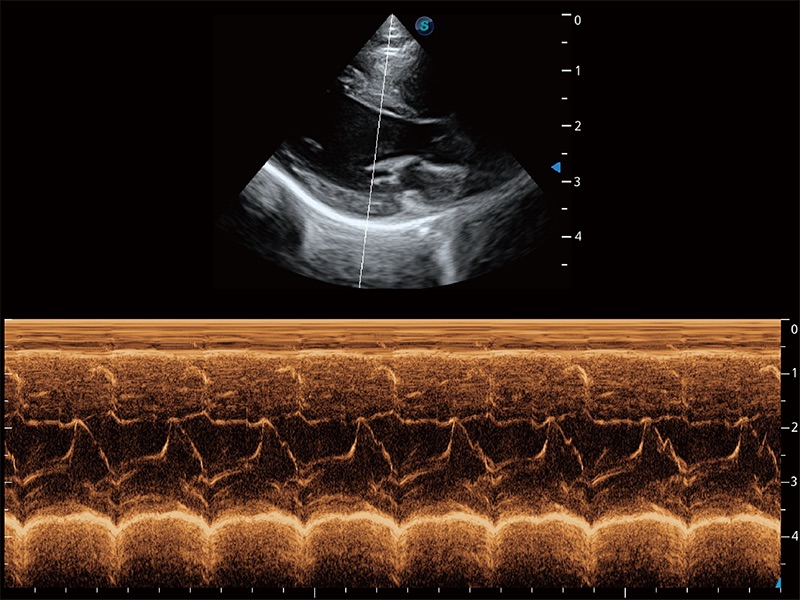

ProPet 80 配备了丰富的心脏探头群、先进的成像技术和专业的心脏测量工具,可帮助动物医生为不同体型和生理结构的动物提供心脏和心肌功能的全面评估。

实时用颜色表示心肌组织运动,观察和定量组织的运动情況,对快速检测与评估心肌的灌注和活性、电传导及心肌收缩和舒张功能等均能提供重要的诊断信息。

通过心肌识别技术与二维斑点追踪技术相结合,对心脏的超声图像进行量化分析。计算心肌17个节段的应变、应变率、速度、位移等,并通过牛眼图的形式进行呈现。

通过360度任意调节3条M型取样线,在同一心动周期上观察心脏不同位置的运动曲线,得到准确的心功能测量数据,有效评估心肌运动及左心室功能。